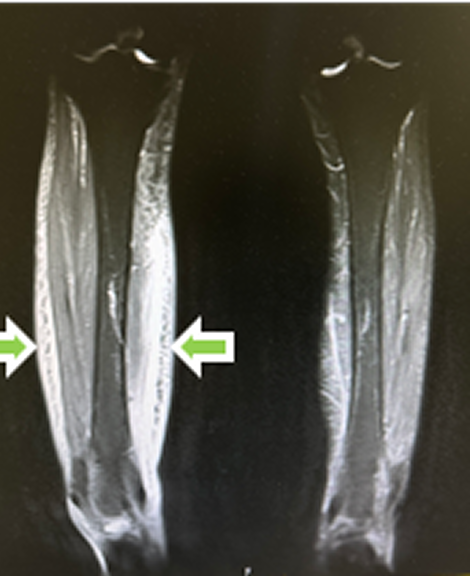

MRI検査

適切な治療にはきちんとした検査が必要です。当院ではより充実した 診断・治療のため、【MRI検査】を積極的に採り入れています。脊椎や関節 (特に膝や肩関節)の痛み・疾患は、MRI検査をお勧めさせていただきます。

MRIは強力な磁石でできた筒の中に入り磁気の力を利用して画像を撮影する検査です。当クリニックでは1.5T(テスラ:磁石の強さ)、ドイツSIEMENS(シーメンス)社製を導入しました。鮮明な画像を撮影できる本機器では脊椎の圧迫骨折などの早期診断が可能なほか、骨・関節・軟部組織など様々な部位や疾患において詳細な画像検査が可能です。MRIは特性上、検査中に騒音が出てしまいますがヘッドフォンにて音楽を聴きながら検査を受けていただくことが可能です。